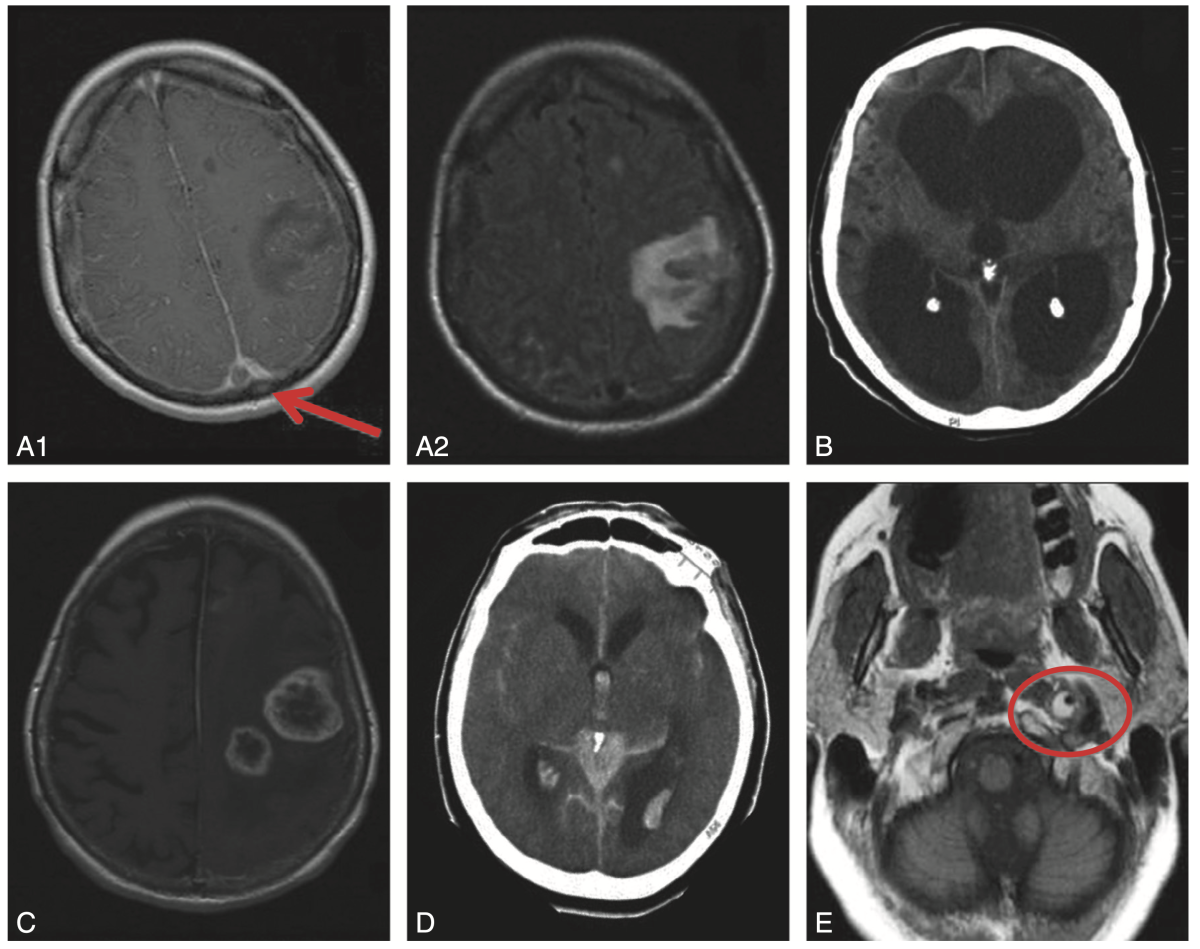

Fig. 9.2.

Exemples d'imagerie cérébrale de céphalées secondaires.

A – TVC du sinus sagittal supérieur. IRM en séquence T1 avec gadolinium (A1 : thrombus responsable d'un signe du delta, flèche) et en FLAIR (A2 : infarctus veineux).

B – Hydrocéphalie (scanner).

C – Tumeur cérébrale (glioblastome) (IRM).

D – Hémorragie sous-arachnoïdienne (scanner).

E – Dissection carotide interne gauche (IRM : hypersignal de la paroi artérielle en « croissant »).

(Source : CEN, 2019.)